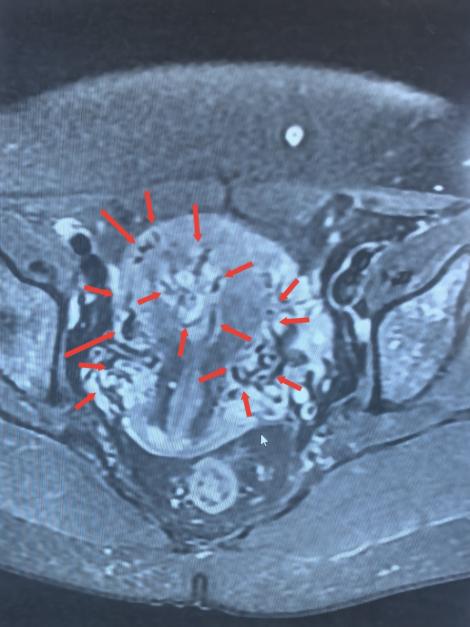

术前检查影像

检查结果很快传来,B超结果显示宫腔内残留组织伴丰富血流,高度怀疑“子宫动静脉瘘”;随后的MRI检查进一步证实,患者宫腔内不仅有异常病灶,邻近子宫前壁还出现多发流空信号——这意味着子宫动脉与静脉之间形成了异常通道,动脉血直接涌入静脉,一旦通道破裂,就可能引发难以控制的致命性大出血。